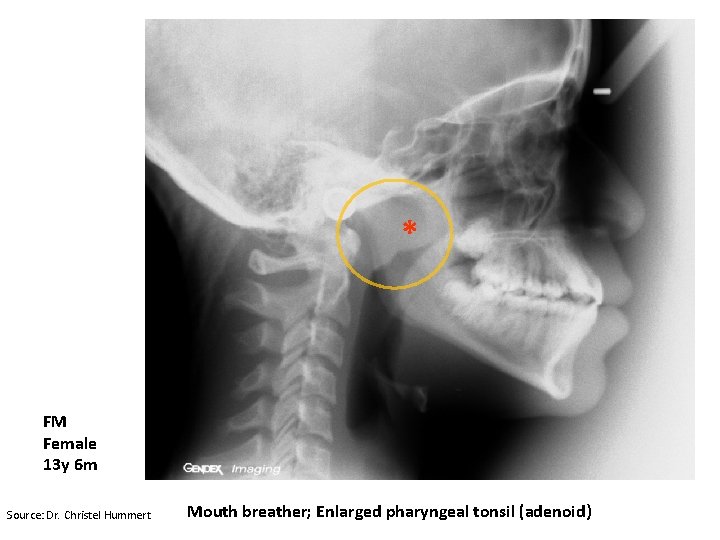

Long-face Syndrome aka “adenoid facies” Increased vertical height in lower third of face Excessive dento-alveolar height “Gummy” smile High arched palate Steep mandibular plane Cause: Nasal obstruction

* FM Female 13 y 6 m Source: Dr. Christel Hummert Mouth breather; Enlarged pharyngeal tonsil (adenoid)